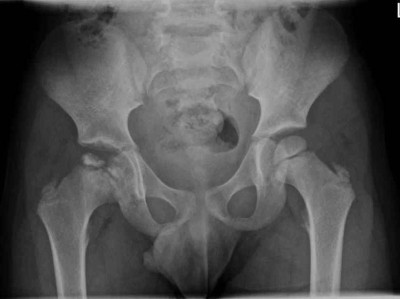

Kleiner Junge humpelt seit Monaten

Ein fünfjähriger Junge bewegt seit Monaten sein rechtes Bein wiederkehrend auffällig – ohne Schmerzen, Verletzung oder erkennbare Entzündung. Eine durchgeführte Sonografie gibt letztlich Anlass für eine sofortige radiologische Abklärung. Was steckt hinter dem ungewöhnlichen Gangbild?

Bildnachweise

Lagerungsplagiozephalus/© Aus Linz et al. Positional Skull Deformities Etiology, Prevention, Diagnosis, andTreatment, mit freundlicher Genehmigung © Deutscher Arzte-Verlag GmbH, Röntgen eines Ellenbogens mit Humerusfraktur/© Sampaio E et al. / all rights reserved Springer Medizin Verlag GmbH, Hüftkopfnekrose eines 13-Jährigen /© Loose O et al. / all rights reserved Springer Medizin Verlag GmbH, Röntgen einer Beckenfraktur und Abdomen-CT bei Jugendlichem/© Karvouniaris N. et al. / all rights reserved Springer Medizin Verlag GmbH, Ausgeprägte fluktuierende okzipitale Schwellung am Kopf eines Babys nach Geburtstrauma/© Härtel C et al. / all rights reserved Springer Medizin Verlag GmbH, Rückenuntersuchung bei kleinem Mädchen/© Viacheslav Lakobchuk / stock.adobe.com (Symbolbild mit Fotomodellen), Schreiendes Baby/© AzmanL / Getty Images / iStock (Symbolbild mit Fotomodell), Gebrochener Arm eines Kindes erhält Gips/© Rafael Ben-Ari / stock.adobe.com (Symbolbild mit Fotomodellen), Kind mit Unterarmfraktur/© DragonImages / stock.adobe.com (Symbolbild mit Fotomodellen), Kind mit Gipsarm/© nycshooter / Getty Images / iStock (Symbolbild mit Fotomodell), Antikörper - Molekül /© luismmolina / Getty Images / iStock (Symbolbild), Adoleszente idiopathische Skoliose/© Springer Medizin Verlag GmbH, Hämatom an der Stirn des 9-Jährigen/© Dr. med. Thomas Hoppen, Morbus Perthes rechts bei 5-jährigem Jungen/© Gemeinschaftsklinikum Mittelrhein, Operative Behandlung des Torticollis muscularis congenitus/© Ploeger M et al. / all rights reserved Springer Medizin Verlag GmbH, Morbus Osgood-Schlatter/© Springer Medizin, Search Icon, Arthropedia, Frau unkenntlich fasst sich ans Knie/© Pornpak Khunatorn / Getty Images / iStock (Symbolbild mit Fotomodell), Ärzteteam führt Hüftoperation durch/© ATRPhoto / stock.adobe.com (Symbolbild mit Fotomodell), Gebrochener Fuß im Gips/© Aleksandr Kirillov / stock.adobe.com (Symbolbild mit Fotomodell)